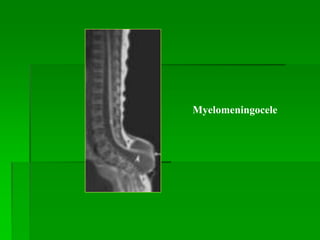

Myelomeningocele  Khiếm khuyết ống thần kinh.

 Thoát vị màng tủy, dịch não tủy, mô thần

kinh ra sau.

 Phần lớn gặp ở thắt lưng, hiếm gặp ở cổ,

ngực.

 Thường kèm:

- Chiari II ( gần 100%)

- Não ứng thủy (80%)

- Tật nứt dọc tủy (30-40%)

- Bất sản thể chai

Myelomeningocele